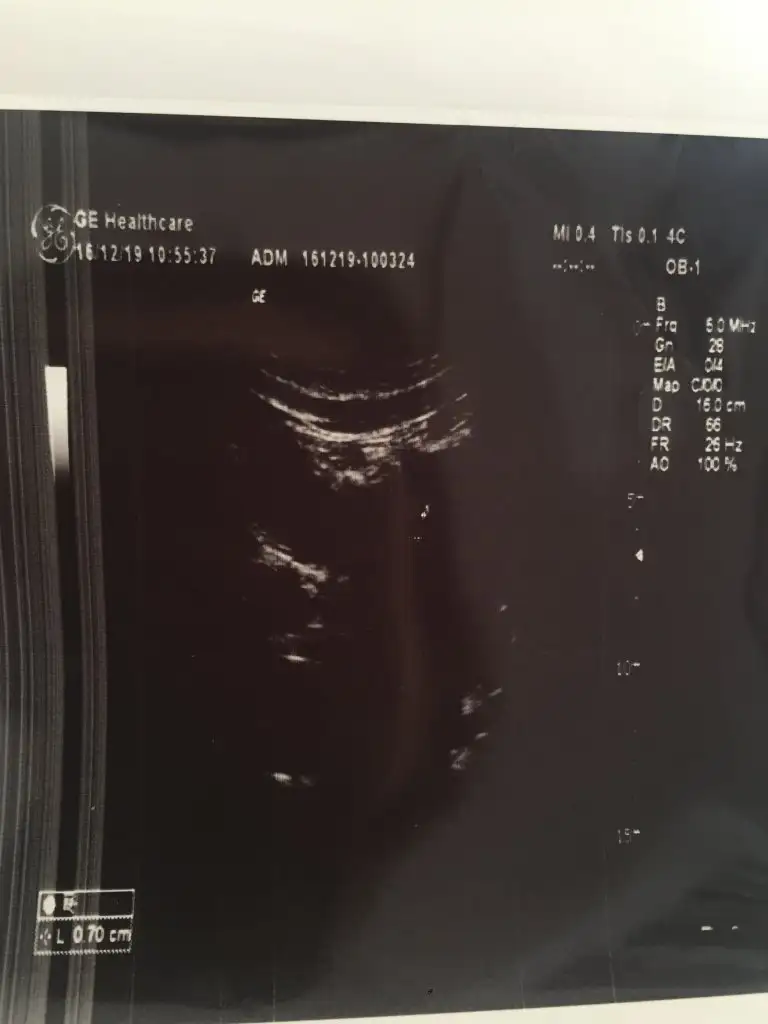

Benim 5+2 gun haftalık:

Eki Görüntüle 2565706

kac haftalik bilmiorum ama beta hcg 900-1000 arasi.karindan bakilan ultrasonda kese oldugu dusunuluyor

IMG_20191216_102203.webp